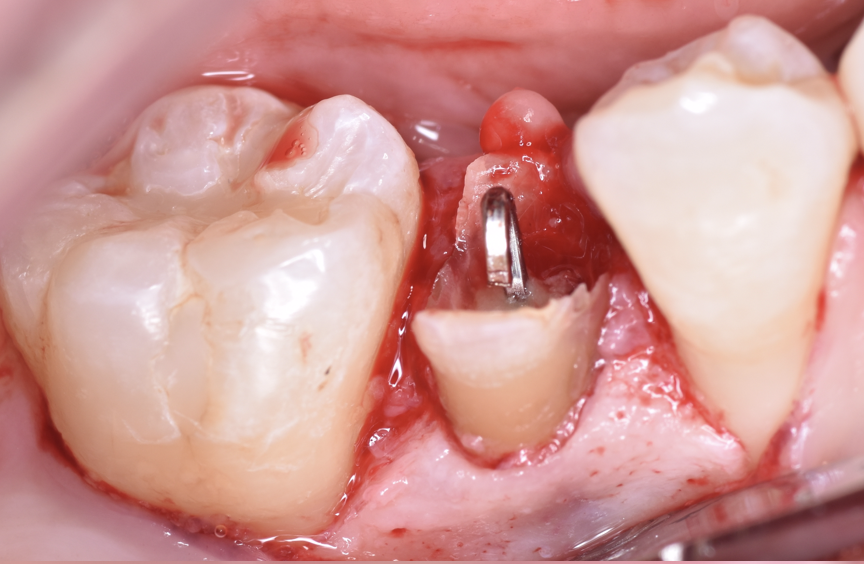

治療前

クラウンレングスニングとは、被せ物を安定して装着するために、歯ぐきや骨の位置を整えて歯の見える部分(歯冠)を長くする外科的処置のことです。

簡単に言うと、「歯ぐきに埋もれて見えない部分の歯を、見えるように出してあげる処置」です。